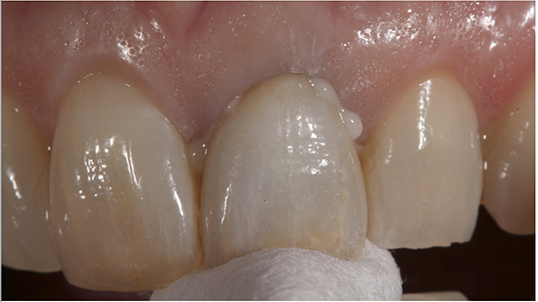

A resin-reinforced glass ionomer cement (GC Fuji PLUS, GC America) was then prepared by activating the capsule with the dispensing gun and placed in the triturator for 10 seconds. The internal aspect of the restoration was then coated liberally with cement (Fig. 10), after which the restoration was immediately seated onto the preparation while maintaining moderate pressure (Fig. 11).

Fig. 11 Fig. 12